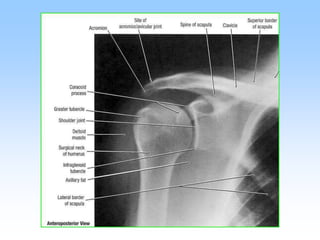

Tư thế chụp

• Thẳng:

– Tư thế chuẩn

– Chụp trước – sau hoặc sau – trước

– Cánh tay xoay trong: chỏm xương cánh tay

hình cầu

– Cánh tay xoay ngoài: rãnh liên củ